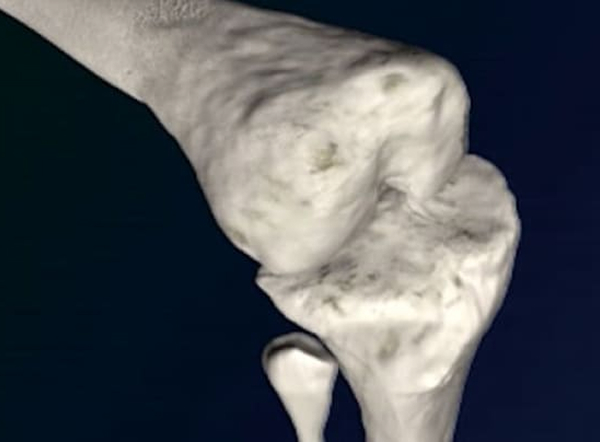

• 変形性股関節症 (術前)

• 骨頭を切除し、大腿骨の内側を整えます。